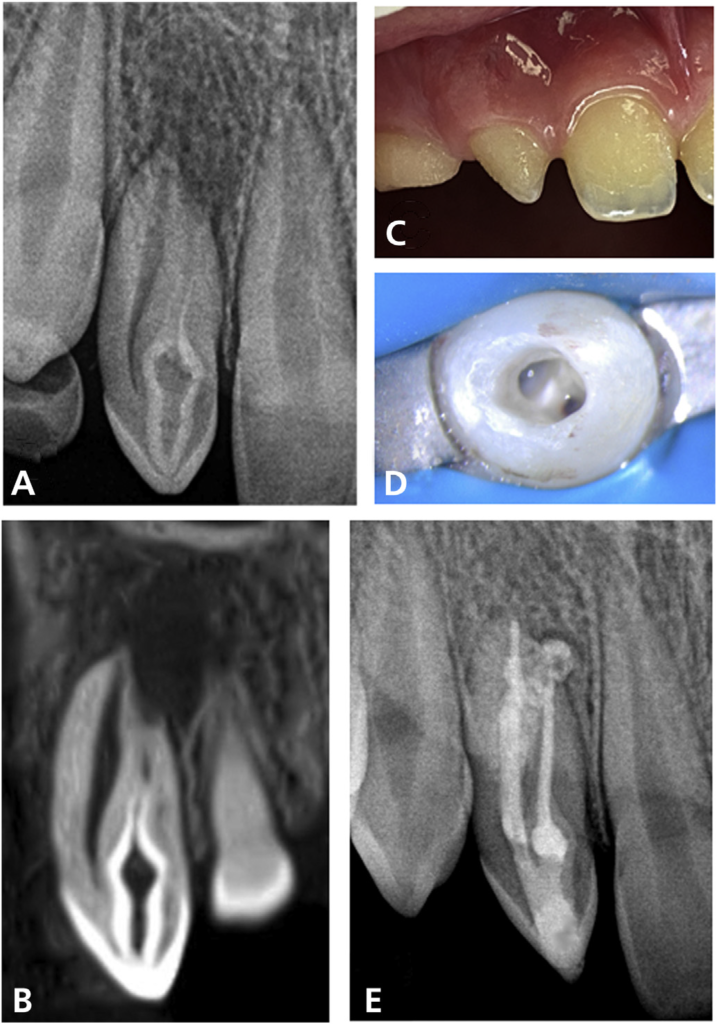

Case Description. Different endodontists treated 6 maxillary incisors with dens invaginatus associated with apical periodontitis. Cone-beam computed tomography was used to help with diagnosis and treatment planning in most patients. Four patients received diagnoses of Oehlers type II dens invaginatus and the other 2 as type III. In some patients with type II, the invagination had to be perforated to permit access to the apical part of the true root canal. Both the true canal and the invagination (pseudocanal) were treated in all cases using an antimicrobial regimen based on chemomechanical preparation with sodium hypochlorite irrigation and supplementary disinfection approaches. Calcium hydroxide medication was used in all but 1 case. The root canal and invagination were often filled using thermoplasticized gutta-percha techniques, sometimes using an apical plug with a bioceramic material in teeth with large apical openings. All treated patients had favorable clinical and radiographic outcomes.

Practical Implications. Regardless of the complex anatomic variations, common strategic therapeutic approaches were identified that might serve as recommendations for proper management of teeth with dens invaginatus and apical periodontitis. These approaches include cone-beam computed tomographic planning, aggressive disinfection using sodium hypochlorite ultrasonic or sonic activation and calcium hydroxide intracanal medication, and thermoplasticized gutta-percha obturation of both the root canal and invagination.